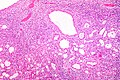

Case 2

| LM | cysts lined by simple epithelium with hobnailing, stroma has an ovarian look (blue, spindle cells) |

- Cysts lined by simple epithelium with hobnailing - key feature.

- Stroma has an ovarian look:

The tumour is predominantly cystic. The cysts are lined by hobnail cells. Ovarian-like stroma is present.